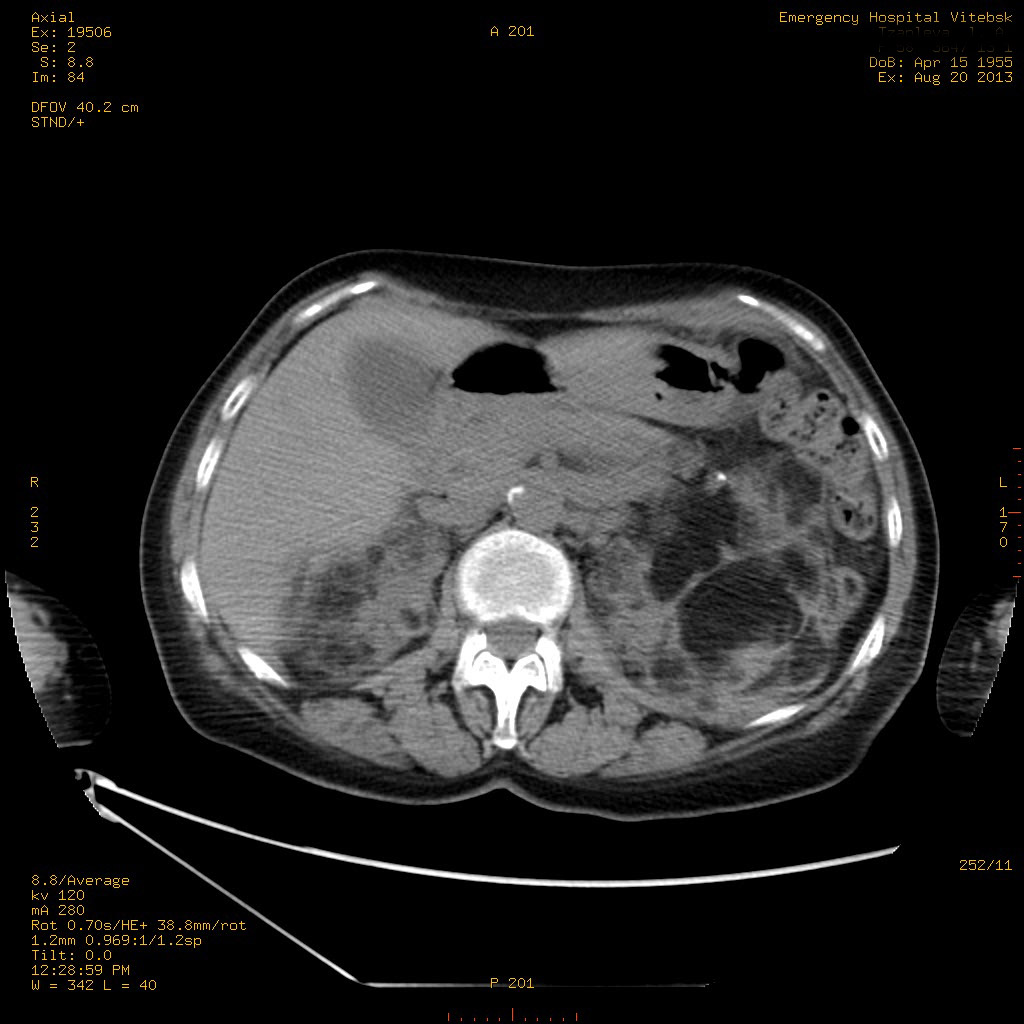

Пожилая женщина с нормальными мочевиной и креатинином.

Ангиомиолипоматоз почек , думаю компонент туберозного склероза.

Да, туберозный склероз.

Случай консультирован на кафедре радиологии Католического университета г.Лёвен (Бельгия) - зав каф. профессор Р.Оуен.